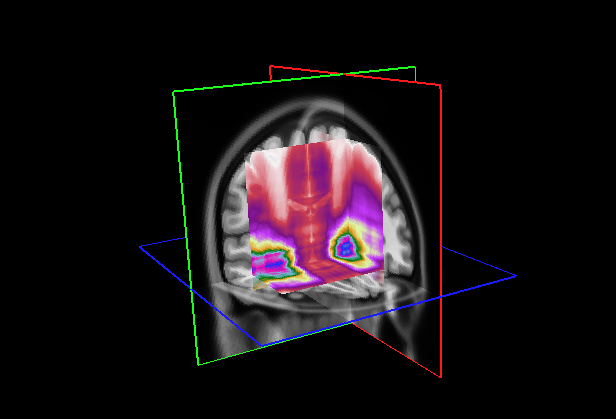

Refer to caption

Figure 7: (Left) Attention distribution for each plane averaged on all the five test to provide entire dataset distributions; (Right) Visualization of mean 3D attention map of entire dataset overlapped to MNI152 template

This section analyzes the interpretability of our approach and those proposed in (Wang et al., 2024; Altay et al., 2021). Our XAI method described in Section 4.3 allowed us to produce a 3D attentional map starting from the attentional weight distributions of the axial, coronal, and sagittal planes. The authors of AwareNet (Wang et al., 2024) designed the slice-aware module of this network to extract, as in our case, a distribution of attentional weights capable of summarizing the importance of each slice in the decision-making process. As a result, our approach can produce a 3D map also using the model proposed in (Wang et al., 2024).

This subsection examines the visual results and quantitative analysis concerning the brain areas emphasized by each model. Fig. 7, on the left, displays the attentional weight distributions across the three planes, averaged over all five folds of the cross-validation. This averaging provides a comprehensive view of the data distribution across all images in the dataset. Starting from the entire dataset distributions, the 3D attentional map was created as detailed in Section 4.3. The averaged 3D map was enhanced by a factor of 10 and overlaid on the MNI152 template, which is representative of a typical patient’s brain. Combining this template with its corresponding atlas facilitates the identification of regions that, on average, received attention from the models. The right side of Fig. 7 shows the explainable MRI generated. The visual representation also indicates that the network targets the medial temporal lobe region, as suggested by the distributions. This result is confirmed by the quantitative analysis shown in Table 8, which reports the metrics for the 20 more extensive regions selected by our model and by AwareNet. As shown in Table 8(a), the three largest regions focused by our diagnosis model are the hippocampus, the parahippocampus, and the amygdala. In contrast, the 3D attentional map generated with AwareNet appears to focus on different regions. The first 3 regions highlighted are Cerebellum Gray Matter, Lateral Occipital, and Fusiform. The right part of the hippocampus appears only after them. From this result, it is also possible to note that with the same 99.9 percentile threshold for binarization, our model highlights a much more localized region. Specifically, our model selects 17 regions with a strong concentration in the top 14. On the contrary, AwareNet highlights 88 regions, 68 of which have been omitted in the Table 8.